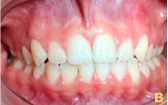

Resolução do caso após a cirurgia

≈